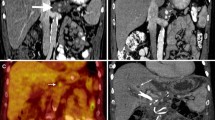

Hepatocellular carcinoma (HCC) is responsible for 80% of the primary hepatic cancers [11], and several ablation options currently exist to treat these tumors. One study analyzed the differences in outcomes between MWA and IRE for patients diagnosed with Child-Pugh B HCC whose tumors were unresectable or treated as a bridge to transplantation [12]. Patients who underwent IRE had shorter post-ablation hospital stays, with an average of one day for IRE patients compared to two days for MWA patients [12]. Only four IRE patients were readmitted for procedure-related issues within 90 days of treatment compared to nine MWA patients, and the most common reasons for readmission included transient liver failure, dehydration, and uncontrolled ascites. Uncontrolled ascites was more severe in MWA patients compared to IRE patients. All of these differences were statistically significant with P≤0.05 [12]. Similar to this study, many other studies have demonstrated that IRE is safe and effective in treating patients with HCC and underlying hepatic dysfunction. Patients who return to IR clinic for post-ablation care usually demonstrate successful treatment of the tumor with no residual enhancement at three months (Fig. 3).

A 49-year-old male with cirrhosis secondary to alcohol use complicated by portal hypertension. MRI of the abdomen with intravenous contrast showed a 2 cm LI-RADS 5 lesion in segment 4 near the hepatic hilum abutting the left and main portal veins. The patient underwent liver-directed IRE after a multidisciplinary tumor board discussion (a) pre-procedural MRI imaging demonstrates an enhancing mass (arrow) near the hepatic hilum. (b) intraprocedural CT imaging demonstrates two parallel probes with an enhancing zone of ablation in between the probes. Gas within the lesion (arrow) is an expected finding due to the dissociation of gases from the blood. (c) post-ablation 3-month follow-up MRI reveals hypoattenuation and lack of enhancement of the ablation target (arrow)